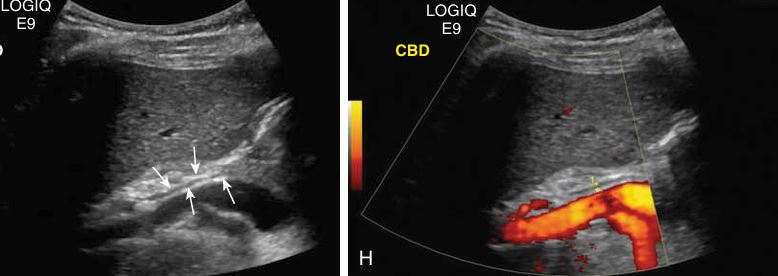

Common Bile Duct doesn’t catch COLOR

SAG - CBD

what plane is this?

transverse

what are the arrows pointing to?

cystic duct

On this sagittal image, the hepatic artery (HA) is shown anterior to the common duct (CD)